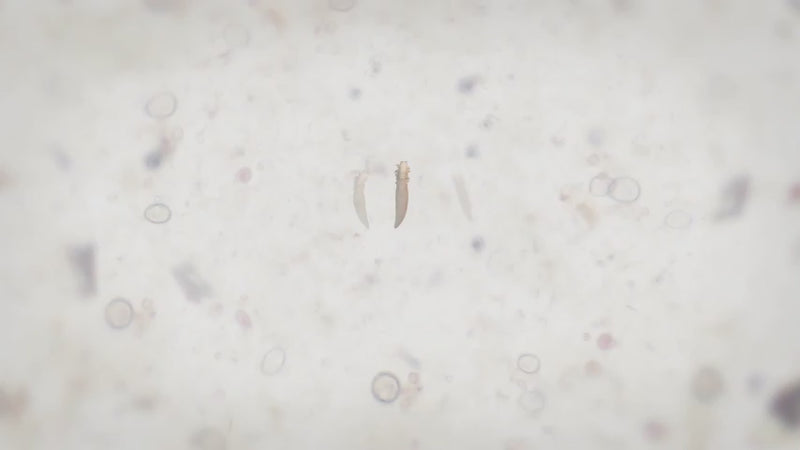

Every day, your eyelids collect a disgusting mix of bacteria, dead skin cells, oil, makeup residue, and tiny mites called Demodex.

These mites literally live on your lash line and feed on the oil in your glands. Over time, all this buildup clogs your meibomian glands, the tiny oil glands in your eyelids that are supposed to keep your tears from evaporating too fast.

When those glands get blocked, your tears dry up in seconds. And that's when the burning, redness, and irritation start. The Blinkjoy system works in two simple steps.

First, you apply the HOCl Gel Cleanser to the Electric Eyelid Brush. Hypochlorous Acid is a powerful antimicrobial agent that kills bacteria and Demodex mites on contact, it's the same stuff your immune system makes to fight infections.